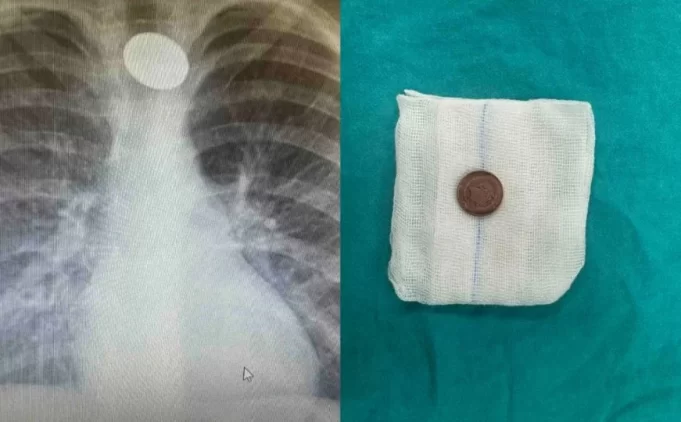

Šesnaestomjesečnom dječaku je u četvrtak, 30. maja, hirurškim putem iz jednjaka uklonjen novčić od 10 feninga.

Pejić je objasnio da je dječak u igri sa stola uzeo kovanicu i progutao je, nakon čega je povraćao nekoliko puta. Srećom, nije dolazilo do gušenja, niti je dječak gubio svijest ili imao problema sa disanjem. Roditelji su se na vrijeme javili u bolnicu, gdje je utvrđeno prisustvo stranog tijela u jednjaku.

Nedugo nakon ovog incidenta, u urgentni blok bolnice stiglo je petogodišnje dijete sa sumnjom da ima strano tijelo u jednjaku. Roditelji su rekli da je dječak odmah nakon večere progutao kovanicu, ali nije imao nikakve tegobe. Nakon dijagnostičke obrade, iz jednjaka mu je uklonjena kovanica od 10 feninga.